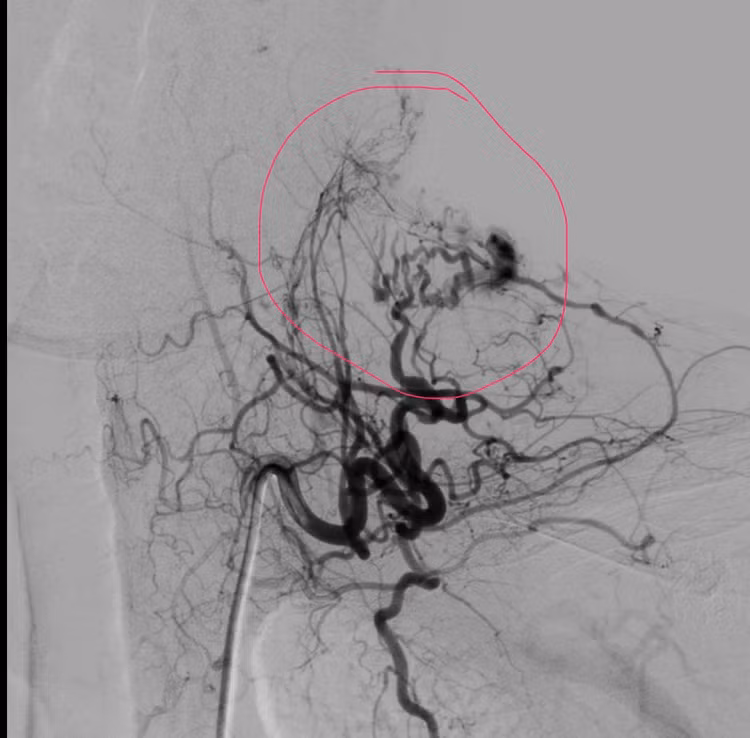

Qua thăm khám lâm sàng kết hợp chụp MSCT, các bác sĩ ghi nhận ổ dị dạng động – tĩnh mạch (AVM) dạng nidus lan tỏa nằm ở phần mềm dưới da vùng cổ. Trước tính chất phức tạp của tổn thương, người bệnh nhanh chóng được hội chẩn đa chuyên khoa, thống nhất chỉ định chụp mạch số hóa xóa nền (DSA) và can thiệp nút mạch cầm máu.

Kết quả chụp DSA cho thấy ổ dị dạng được nuôi dưỡng bởi nhiều cuống mạch xuất phát từ thân giáp cổ, kèm theo hệ tĩnh mạch dẫn lưu nông giãn lớn lan vùng cổ, vai, lưng, làm tăng nguy cơ chảy máu tái phát nếu không xử trí triệt để.

Dưới hướng dẫn hình ảnh chính xác, ê-kíp đã tiến hành nút tắc chọn lọc từng cuống mạch nuôi bằng keo sinh học, giúp giảm rõ rệt dòng chảy trong ổ dị dạng. Sau can thiệp, người bệnh được khâu vết rách da, băng ép tại chỗ, tình trạng chảy máu cơ bản được kiểm soát hoàn toàn. Toàn trạng ổn định, người bệnh được chuyển về Hồi sức cấp cứu để tiếp tục theo dõi sát.